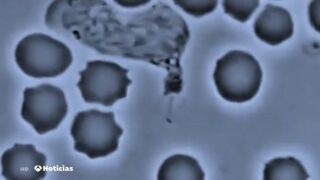

Más de 26 mil personas morirán este año en nuestro país por infecciones causadas por bacterias multi-resistentes a los antibióticos. EL dato lo aporta la Sociedad Española de enfermedades infecciosas. Además, este 2019 estas bacterias multiplicarán por 22 las muertes en accidentes de tráfico.

Según las estimaciones de la Sociedad Española de Enfermedades Infecciosas, con datos de 133 hospitales, 221.958 pacientes sufrirán una infección por bacterias multirresistentes.

Este registro "confirma la magnitud y la gravedad" de las infecciones por bacterias multirresistentes en España, así como los datos de estimaciones de muertes del año pasado, que cuantificaron más de 35.000 fallecimientos. La SEIMC califica como "una amenaza de salud pública de primera magnitud" el problema de la resistencia a antibióticos, y avisan de que España aún tiene tareas pendientes.